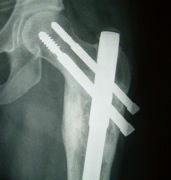

ORIF and bone graft

Indication

- fracture

- weight bearing bone